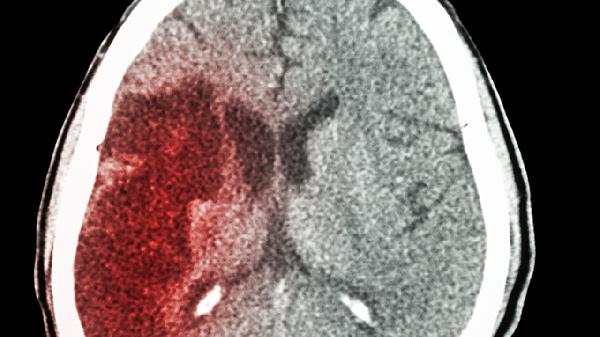

脑出血可通过保持呼吸道通畅、控制血压、预防并发症、康复训练、心理疏导等方式护理。脑出血通常由高血压、脑血管畸形、外伤、血液病、动脉瘤破裂等原因引起。

脑出血恢复期需保持低盐低脂饮食,每日钠摄入不超过3克,多吃西蓝花、深海鱼等抗氧化物丰富的食物。遵医嘱服用阿托伐他汀钙片控制血脂,定期复查头颅CT。康复训练要循序渐进,避免过度疲劳。注意监测血压晨峰现象,清晨起床时动作宜缓慢。若出现剧烈头痛、呕吐或意识改变需立即就医。